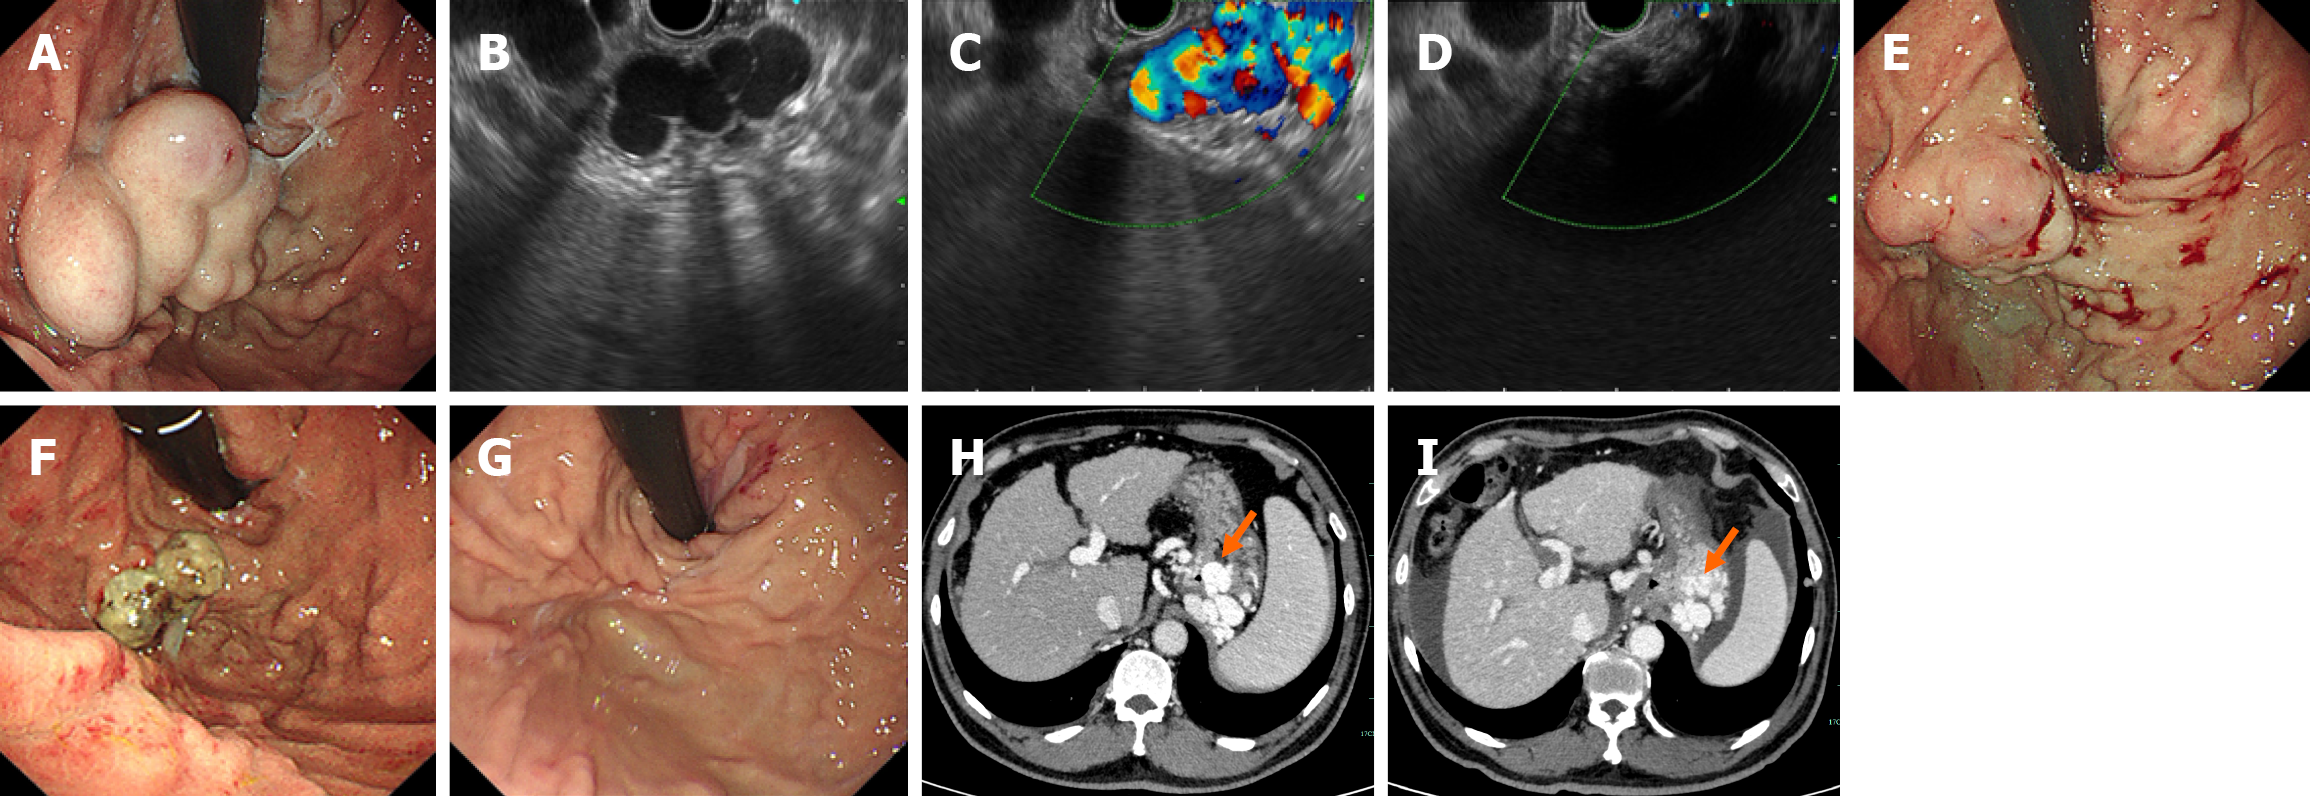

Figure 3 A 54-year-old man with tortuous gastric varices who underwent endoscopic-ultrasound-guided coil and cyanoacrylate injection.

A: Endoscopic examination revealed nodular gastric varices (GVs); B: Endoscopic image of the GV; C: Color doppler image showing flow in the GV; D: Color doppler imaging revealed GVs with no blood flow after the procedure; E: Endoscopic examination immediately revealed GVs with no bleeding after the procedure; F: Endoscopy revealed postinjection ulcers 30 days after the procedure; G: Endoscopy revealed resolution of the GVs 8 months after the procedure; H: Contrast-enhanced computed tomography (CT) scan showing GVs (orange arrow); I: Contrast-enhanced CT review revealed that the GVs had disappeared; the coliform (orange arrow) could still be observed 1 week later.